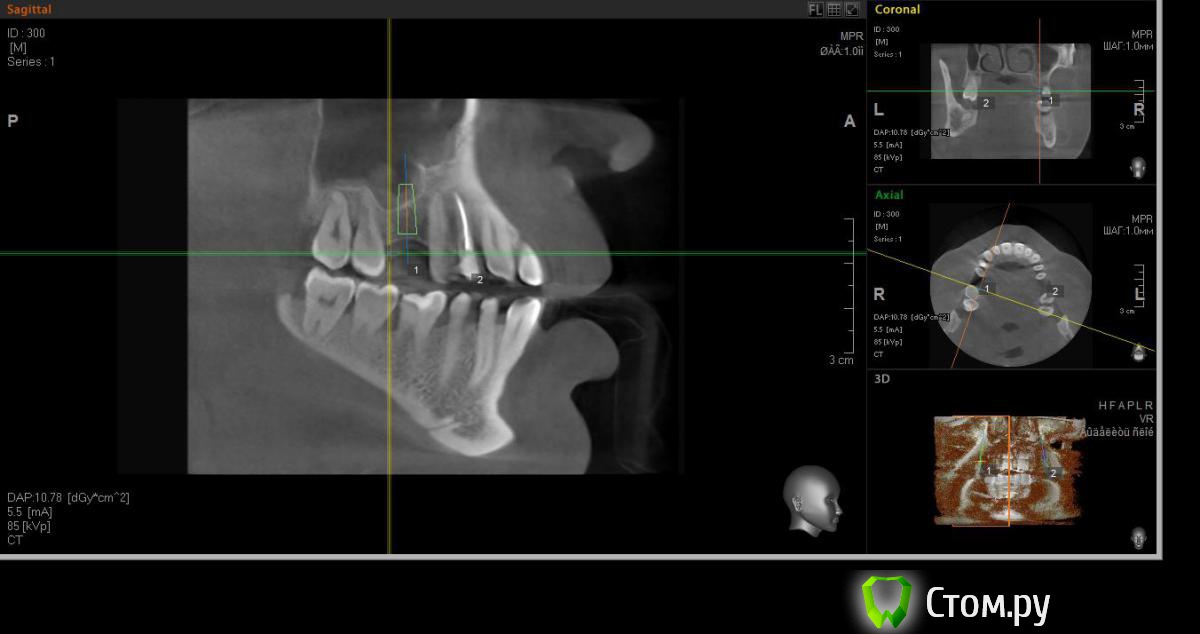

faity Опубликовано 18 мая, 2014 Автор Поделиться Опубликовано 18 мая, 2014 хочу вот так сделать, на 1.6 мягкий лифт, в обл 2.6 не лезтьвинты Ankylos 1.6- 4,5/11 2.6- 3,5/9,5кости в области 1.6- 7,5мм, должно хватить для закрытого, открытый пациент не потянет по финансам.какие мысли? Ссылка на комментарий